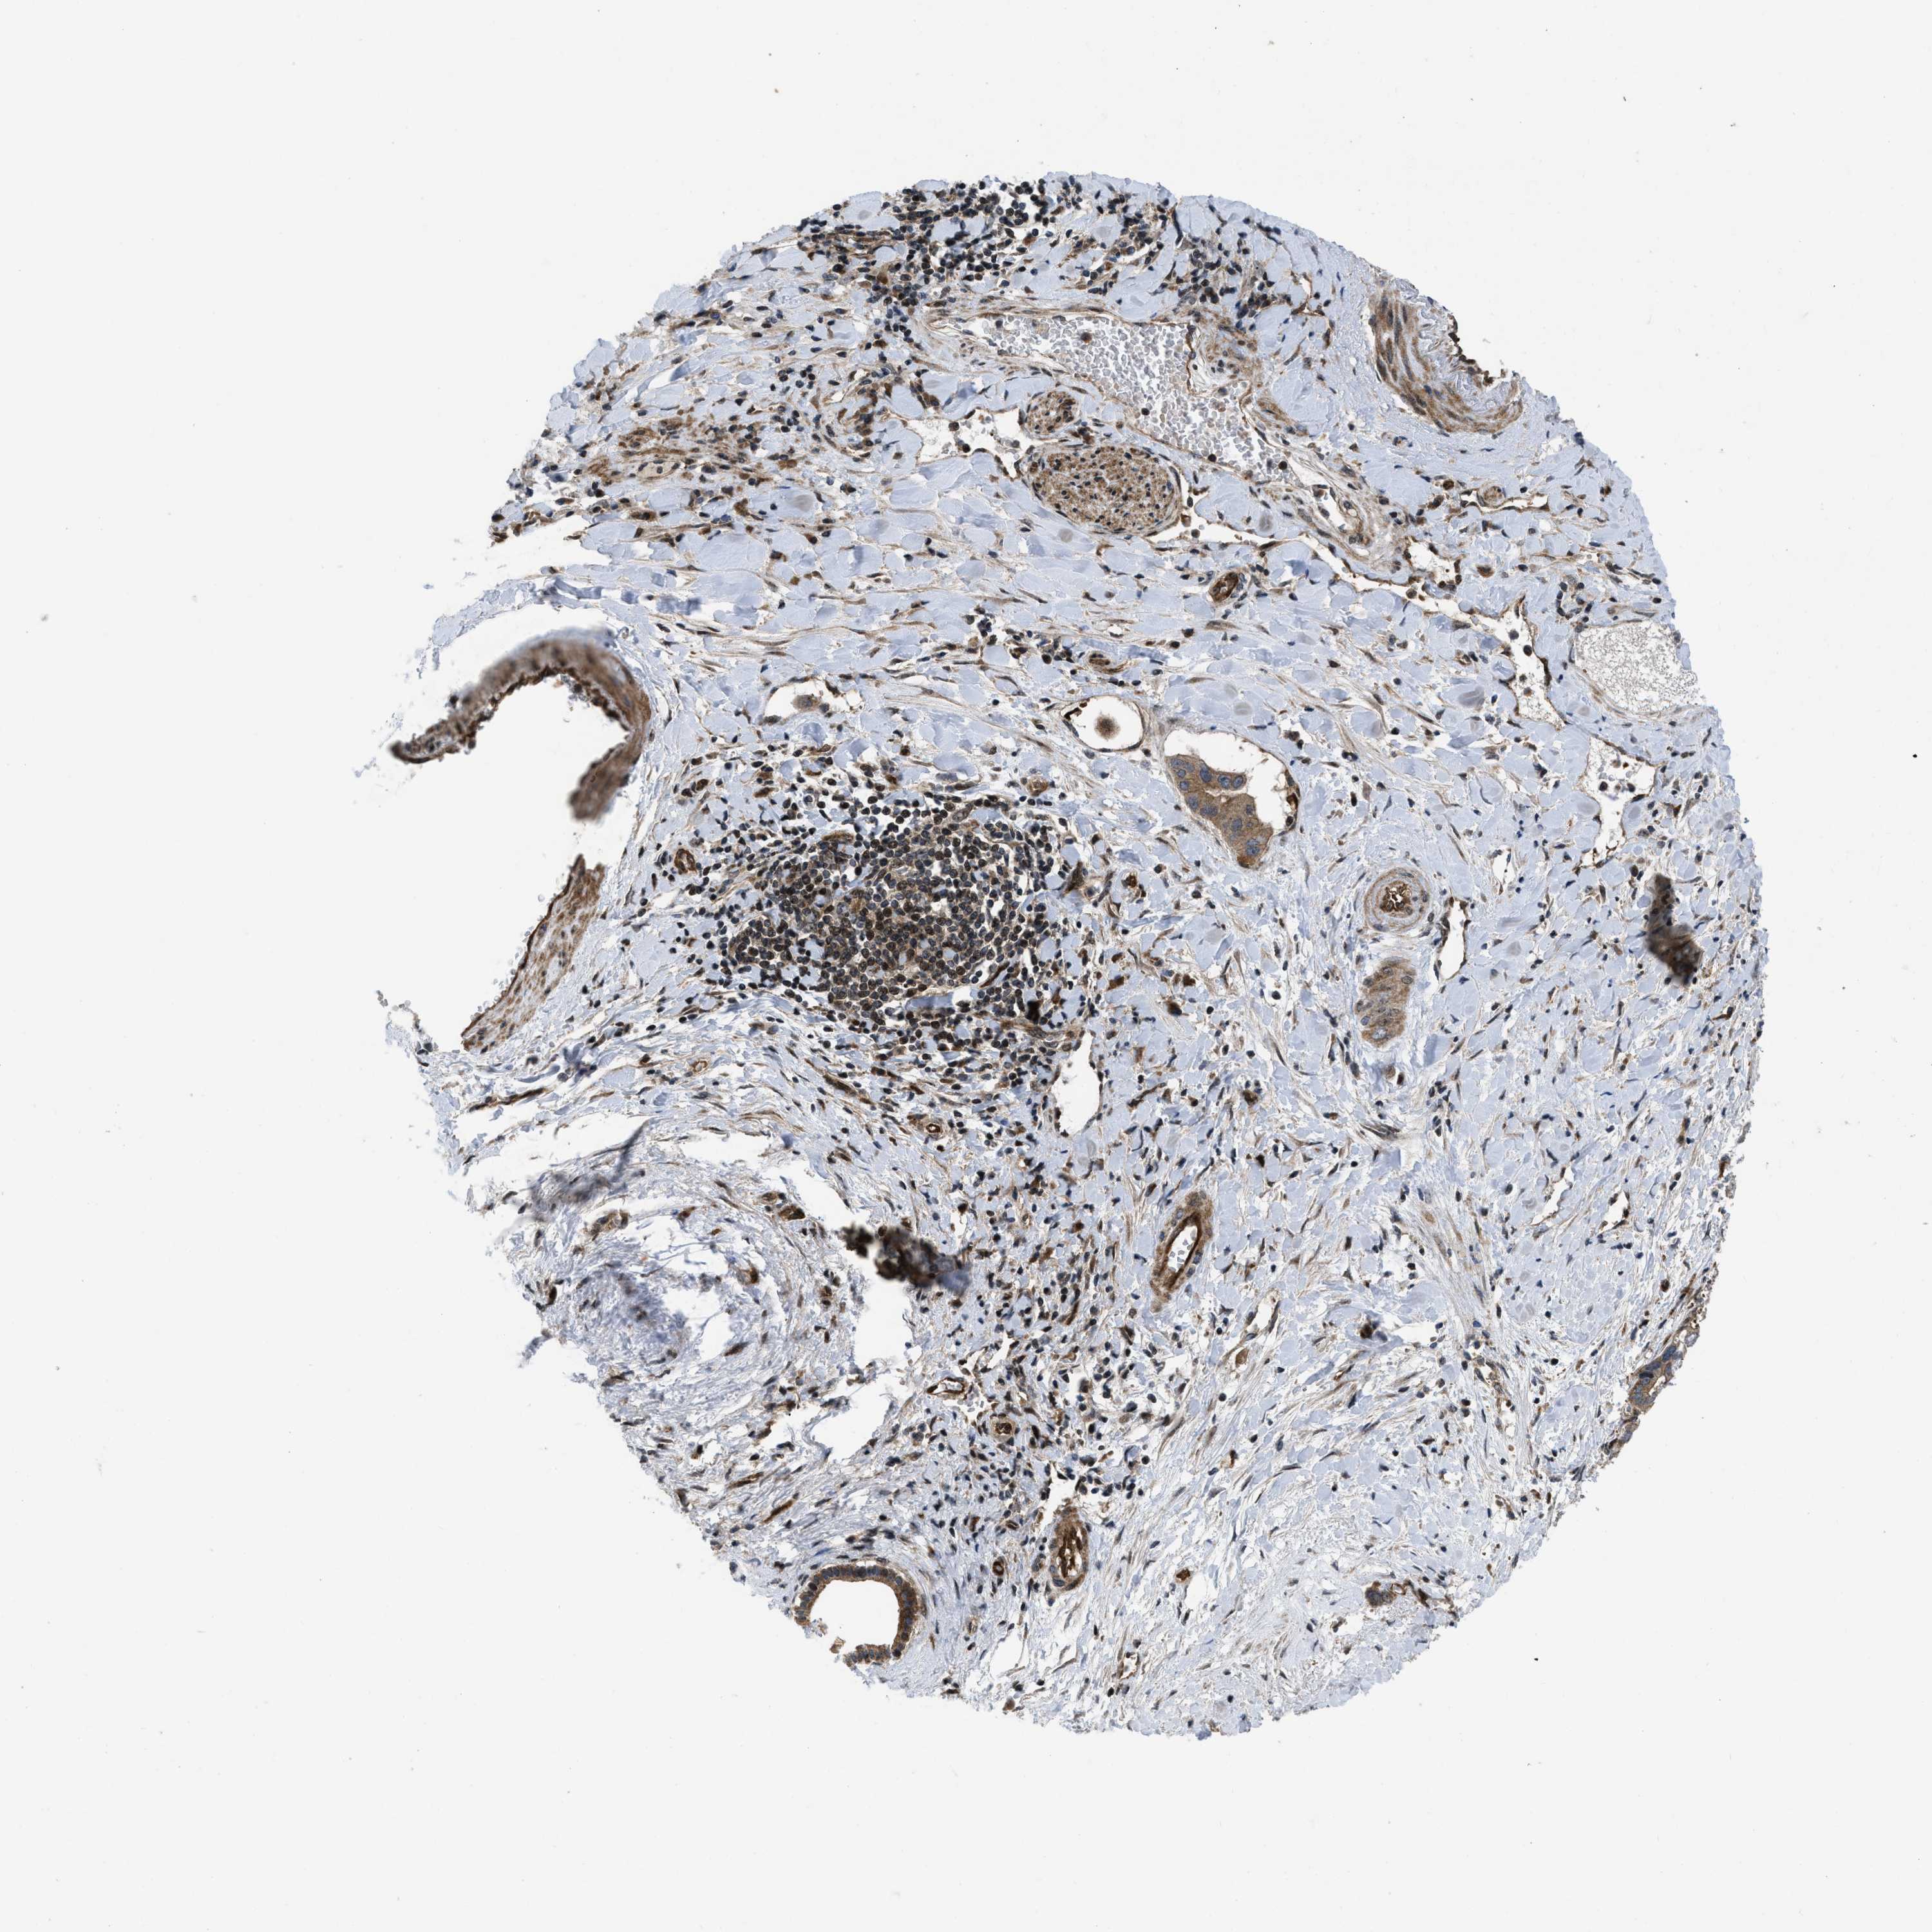

LIVER CANCER - Protein expressioni

A mouse-over function shows sample information and annotation data. Click on an image to view it in a full screen mode. Samples can be filtered based on level of antibody staining by selecting one or several of the following categories: high, medium, low and not detected. The assay and annotation is described here.

Note that samples used for immunohistochemistry by the Human Protein Atlas do not correspond to samples in the TCGA dataset.

Antibody stainingi

Antibody staining in the annotated cell types in the current human tissue is reported as not detected, low, medium, or high, based on conventional immunohistochemistry profiling in selected tissues. This score is based on the combination of the staining intensity and fraction of stained cells.

Each image is clickable and will lead to virtual microscopy that enables deeper exploration of all samples and also displays staining intensity scores, fraction scores and subcellular localization as well as patient and tissue information for each sample.

Antibody HPA043236

Antibody CAB018600

Staining

High

Medium

Low

Not detected

Intensity

Strong

Moderate

Weak

Negative

Quantity

>75%

75%-25%

<25%

None

Location

Nuclear

Cytoplasmic/membranous

Cytoplasmic/membranous,nuclear

Cholangiocarcinoma

Carcinoma, Hepatocellular, NOS